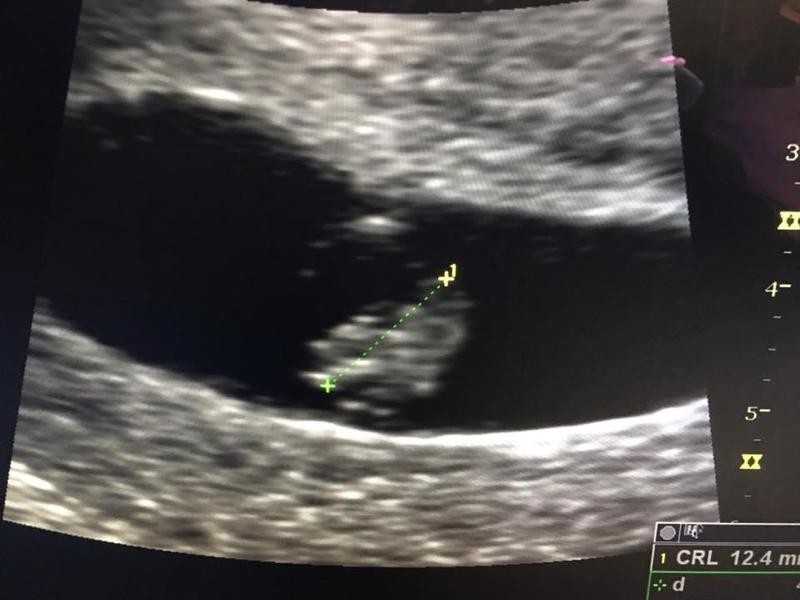

鄭醫師在《今天我救了一個人,同時殺了一個來不及長大的胚胎》一文中提到,38歲的女病人日前去某大醫學中心產檢,醫師幫她做生平第一次子宮頸抹片檢查,發現有子宮頸腺癌1B1期,患者上週五(22日)前來看診,尋求協助。